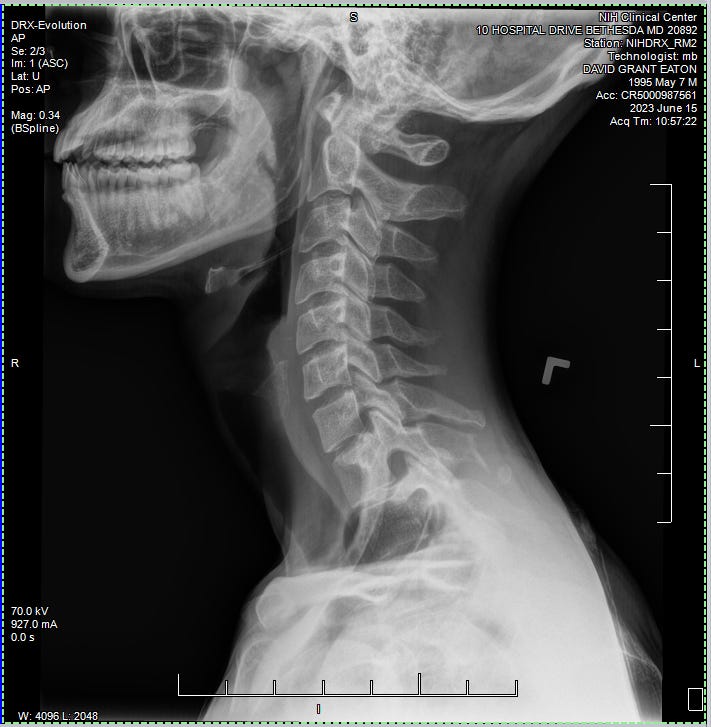

We then headed off of the unit to attend my first rounds of testing. Everywhere I went from this point on required a scan of my wristband, as well as a recitation of my name and date of birth. I did my first ever EKG and Chest X-ray. Zzzzap. I’d never seen such machinery in person before. It was pretty darn cool to see it all in action, and in each of these rooms the operators were super kind and clearly well experienced in their respected fields. I was also surprised that there wasn’t much waiting for these tests. I’m assuming that this study had some kind of priority to move things along rather quickly.

Ann came back to check on me at some point. She was delighted to share that my COVID test came back negative, which meant I was now free to go about the common areas of the unit. She also mentioned that I was welcome to attend my first evening group, which started at 6:45pm. Our last order of business was to go through a simple MRI screening. She went down a long list of questions, relating to any kind of metal that may have found its way into my body. Pacemakers, titanium plates, that kind of stuff. Most of these things I had never even heard of. So we quickly made our way through the list, until towards the bottom she asks: “ever been shot with a BB gun?”

I tell a story from back in 4th grade I think it was. When one of my closest friends “accidentally” shot me in the neck with his Red Ryder BB gun while we were hanging out in his backyard one night. It was an honest mistake, I’m sure. But Damn did that hurt, and boy

did he get a kick out of that story when he came to visit later that weekend.

She went ahead and scheduled another X-ray for me, just to be sure there wasn’t any kind of shrapnel left over from the incident. Fortunately none was found, and now I have this sick X-ray as a momento